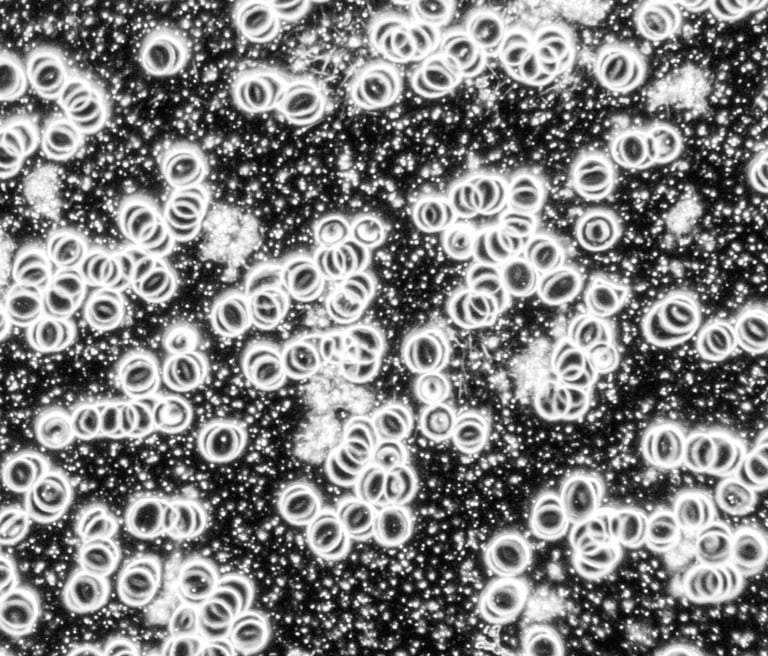

1. Levend Bloed Analyse

Analyseer uw gezondheid met onze unieke donkerveld microscooptechniek voor diepgaand inzicht